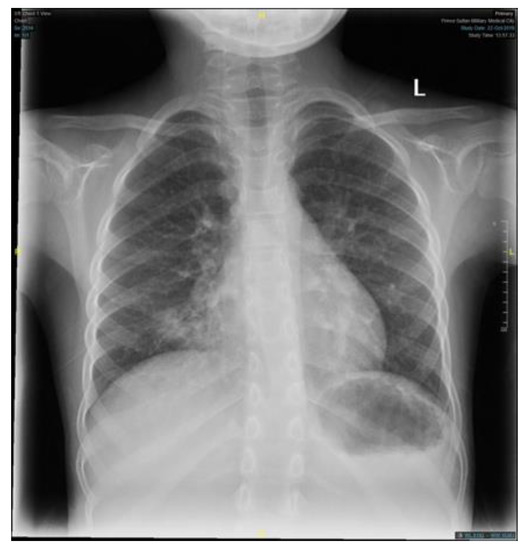

The patient condition necessitated a multidisciplinary approach, involving several sub-specialties, and requiring multiple laboratory workup and diagnostic procedures. Her initial workup, constituting of full blood count, electrolyte, and blood gases, were all within normal limits (Table 1). Similar to the findings of her primary treating hospital, her chest x-ray showed patchy infiltrates, primarily over the lower zones (Figure 2). It was consistent with the results of the computed tomography (CT) scans of the chest, which illustrated the presence of bronchiectasis involving the lower zones (Figure 3). Moreover, she underwent bronchoscopy and bronchoalveolar lavage a few days after starting antibiotics. Bronchoscopy findings showed mild erythematous change of the airway with no purulent secretions distally, while the lavage showed no growth of any bacterial organisms, including acid-fast bacilli. Although endoscopy failed to demonstrate any anatomical abnormality, severe reflux was noted on the barium swallow test (Figure 4). To assess the copious nasal discharge, the patient underwent a CT sinus scan and nasopharyngeal scope, confirming the diagnosis of infectious ethmoid and maxillary sinusitis on a background of allergic rhinitis. Immunological workup was carried out to rule out any primary immunodeficiency conditions, including lymphocyte subsets, immunoglobulin subclasses, tetanus, and diphtheria antibodies. All tests, except the lymphocyte subsets, demonstrated a normal result (Table 1). The standard spirometry showed mild partially reversible obstructive airflow limitation with FVC 75%, FEV1 of 65%, FEV1/FVC 71% and mid-expiratory airflow of 45% with 20% improvement post-challenge with bronchodilator.

Figure 2. A plain chest X-ray, an anteroposterior film, showing a radioopaque opacity infiltrate seen over the right and left lower zone with mild hyperinflation. (L = Left).